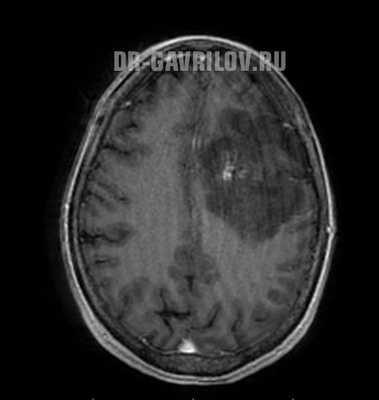

- Магнитно-резонансная томография - способна провести визуализацию опухоли в любом отделе головного мозга, выявить размер и пределы образования. В 98% случаях МРТ позволяет поставить точный диагноз. При необходимости процедура может проводиться с контрастом, что еще больше увеличивает информативность исследования.

- компьютерная (КТ) и магнитно-резонансная томография (МРТ) с контрастом - золотой стандарт при обследовании головного мозга, получаются высокоточные послойные изображения;